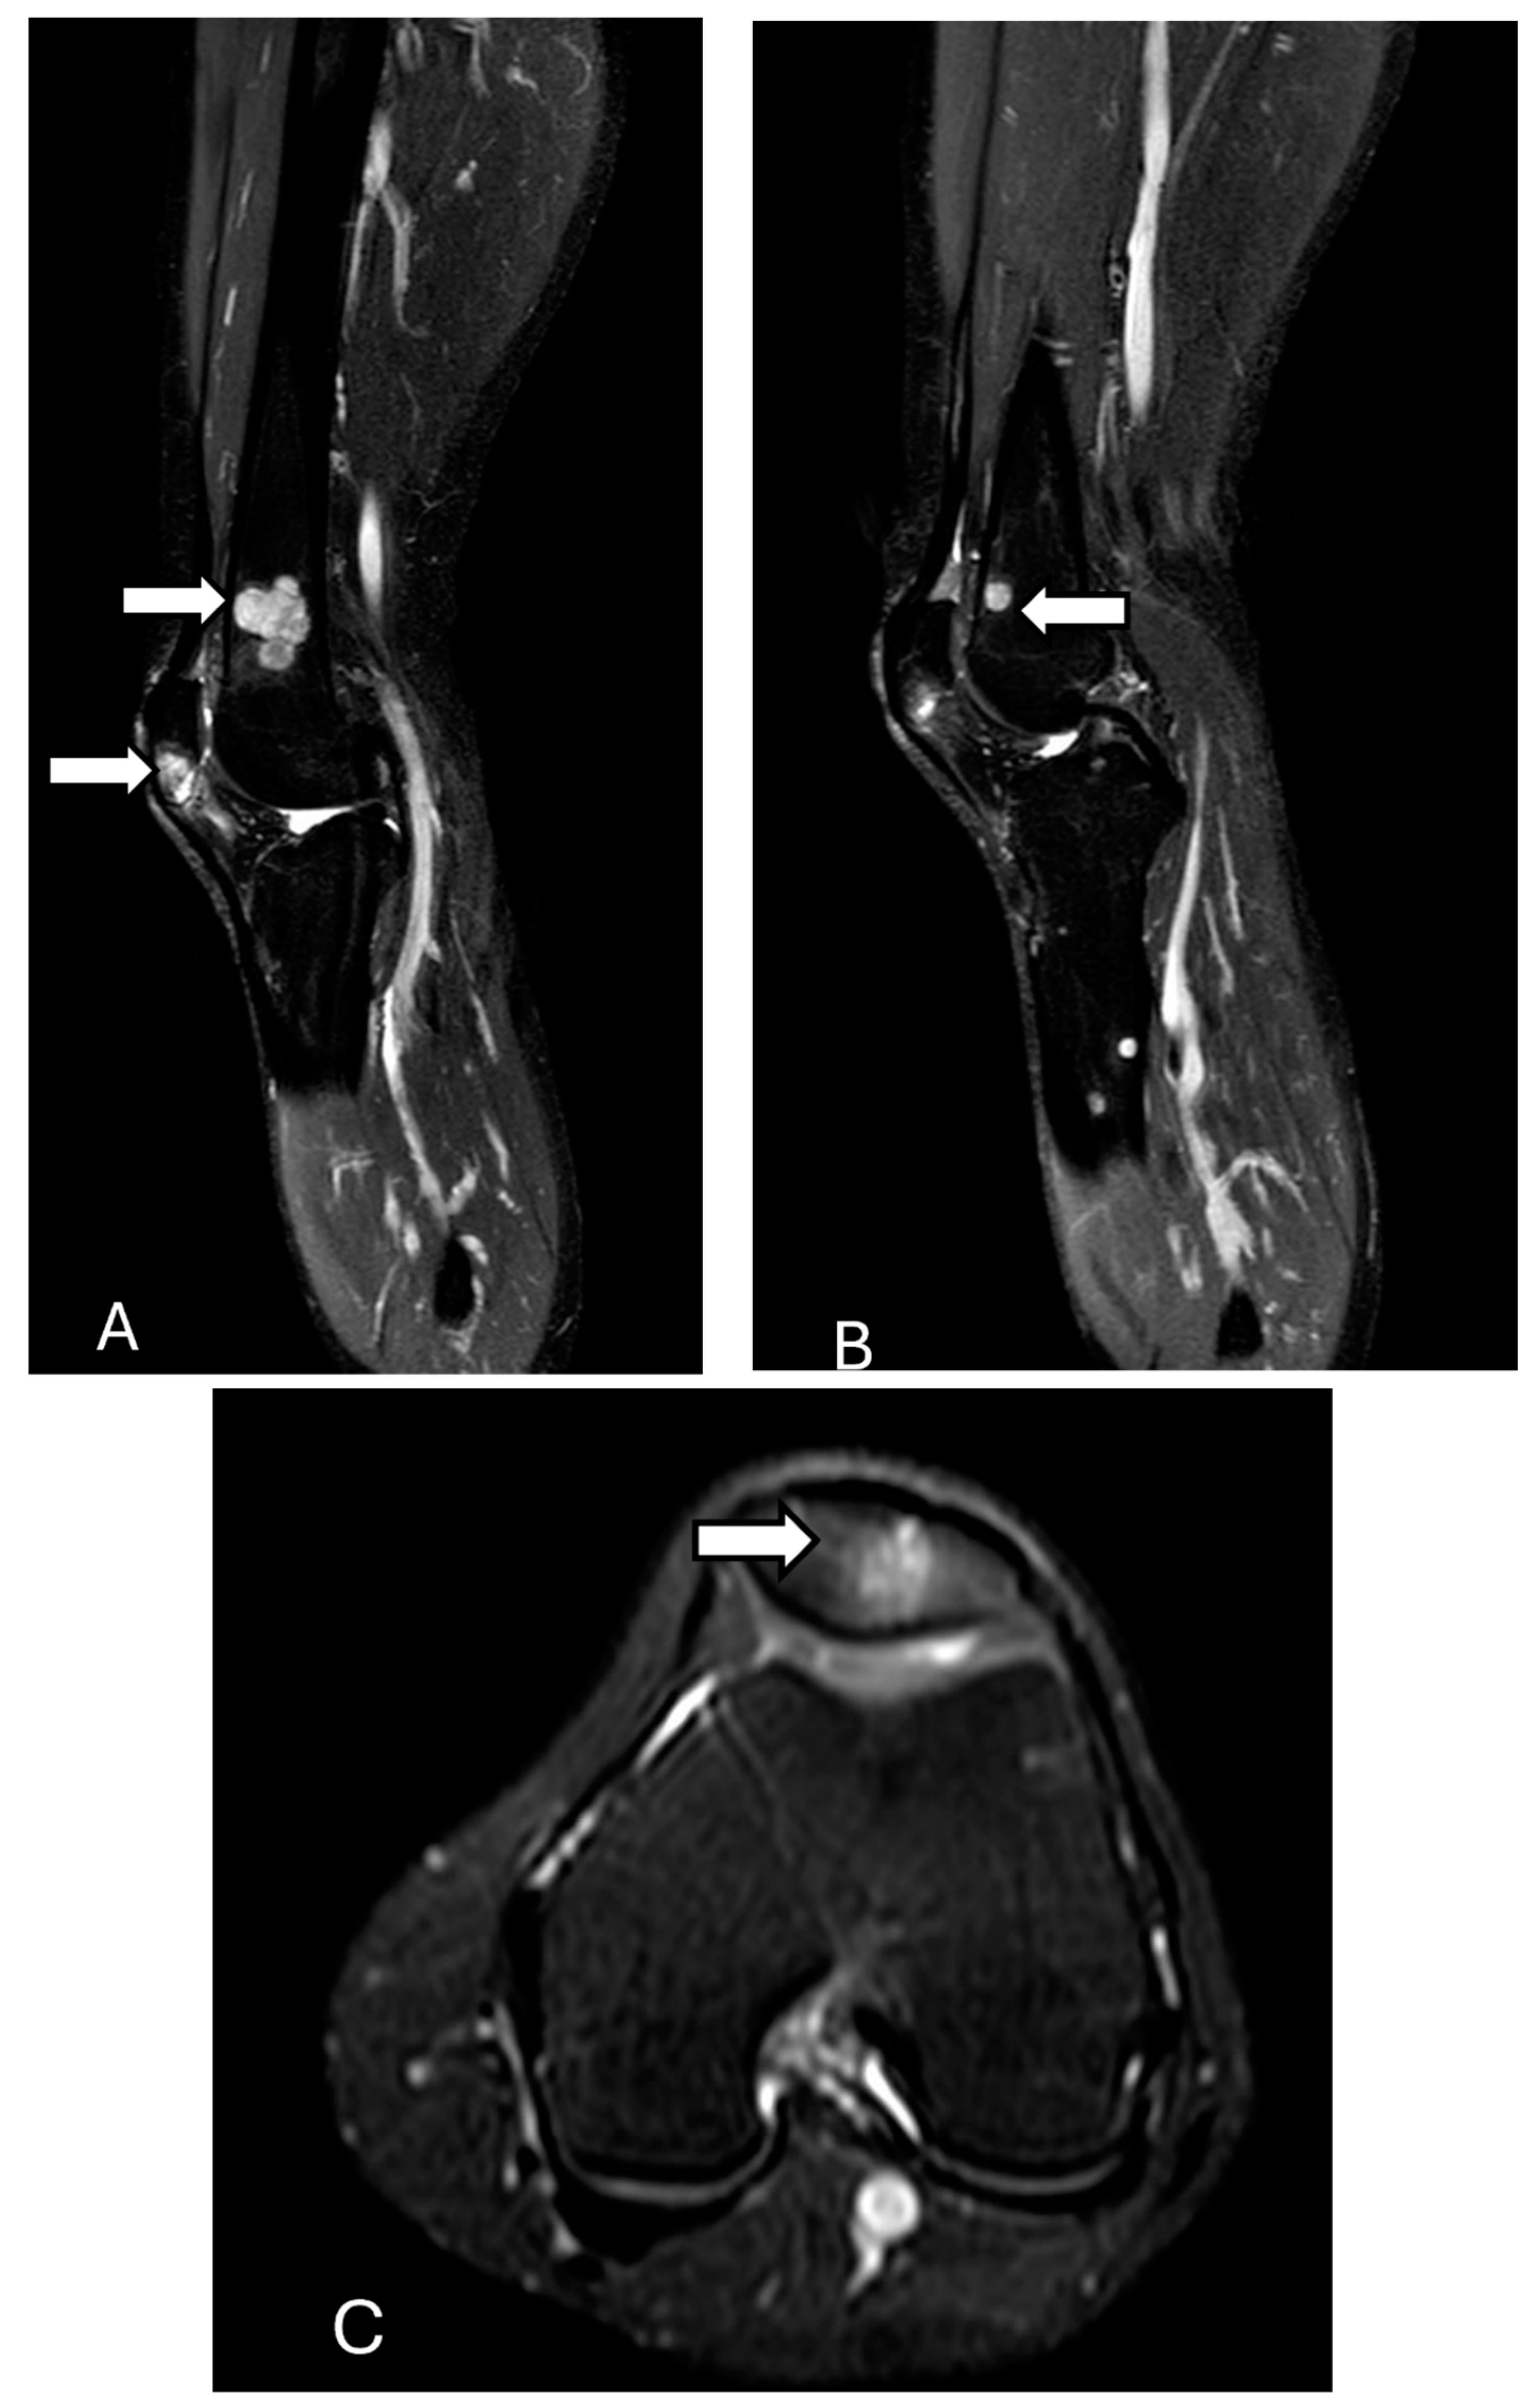

3.10. Metabolic Diseases